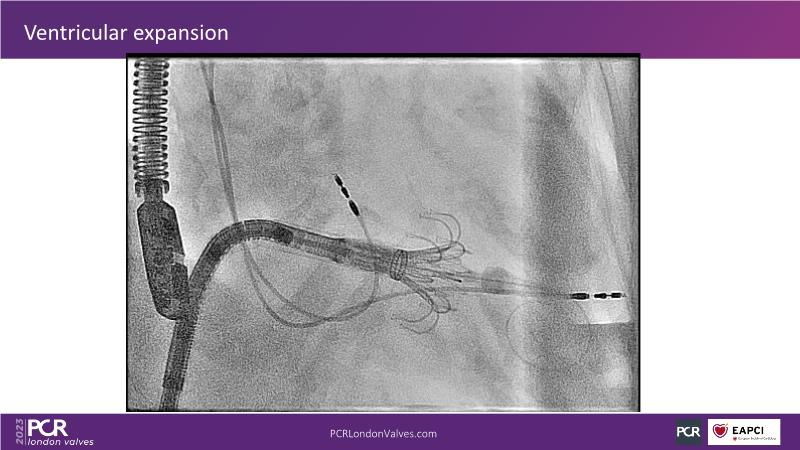

This session explores the features of the PASCAL Precision and the EVOQUE tricuspid replacement systems through simulators and case presentations, while a panel of experts discuss the technology, witnessing live demonstrations of treating mitral and tricuspid regurgitation patients.

- To introduce the EVOQUE tricuspid replacement system showcased with a simulator and a case presentation